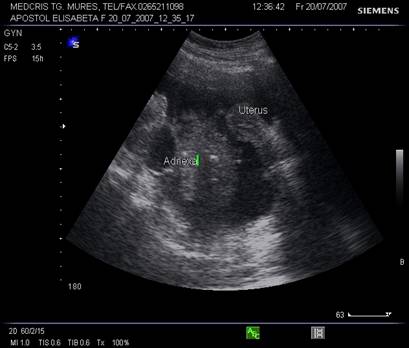

Fig. Nr.341. Sectiune longitudinala prin pelvisul feminin

Fig. Nr. 342. Pelvis feminin vazut dispre peretele abdominal